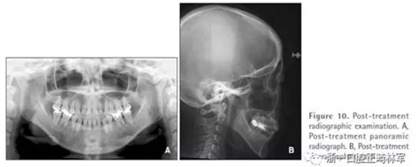

全景片顯示上前牙區(qū)未發(fā)生進行性牙根吸收。然而,在下磨牙區(qū)有輕度牙根吸收,并且牙根平行性有改善空間(Figure 10A)。

頭測顯示:下頜平面角從46.7°減小到44.0°。上頜第一磨牙高度減小1.2mm。面高有減小(N-Me: 133.2 mm to 127.7 mm, Ans-Me: 78.5 mm to 72.6 mm; Table 1,Figures 10B and 11)。上下頜切牙顯示腭側(cè)和舌側(cè)傾斜(U1-SN: 95.8°to 91.8°, IMPA: 83.7°to 77.7°)。

治療前后頭影疊加圖清楚地顯示,下頜發(fā)生逆時針旋轉(zhuǎn),上下切牙舌側(cè)移動(Figure 11)。CT顯示髁突未發(fā)生形態(tài)改變,而磁共振T2影像顯示有形態(tài)改善(未提供圖像)。在治療期間沒有出現(xiàn)顳下頜關(guān)節(jié)癥狀。